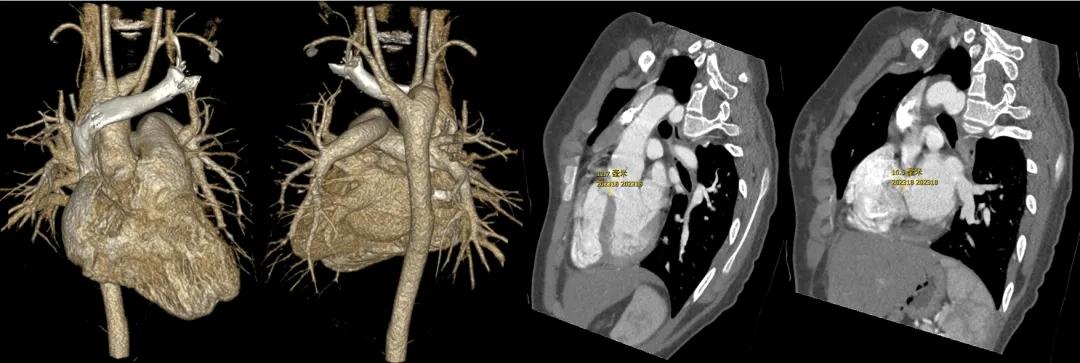

术前造影:室间隔缺损处造影,造影显示有膜部瘤形成,测量缺损大小,左侧基底大小10.8mm,右侧分流口2处,分流大小约2mm。

室间隔缺损介入封堵

根据术前测量和术中造影结果,选择MemoSorb全降解封堵器ABFDQ-Ⅱ08,配合8F可降解封堵器介入输送系统进行封堵。